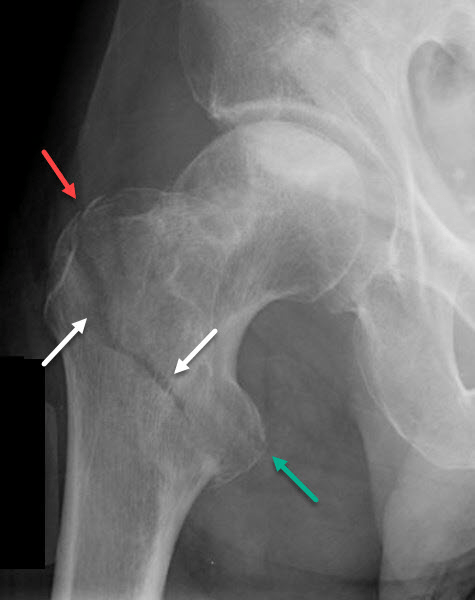

This worrisome (for some) shoulder XRAY actually has TWO associated injuries in one picture?

Anterior shoulder dislocation with Hill-Sach's deformity

This 60kg 8 year old with left hip pain is hopping for an extra scoop?

Left Slipped Capital Femoral Epiphysis (SCFE)

If you can't describe this fracture to your Bone Bro, you're an outdated Stryker part?

Right intertrochanteric fracture